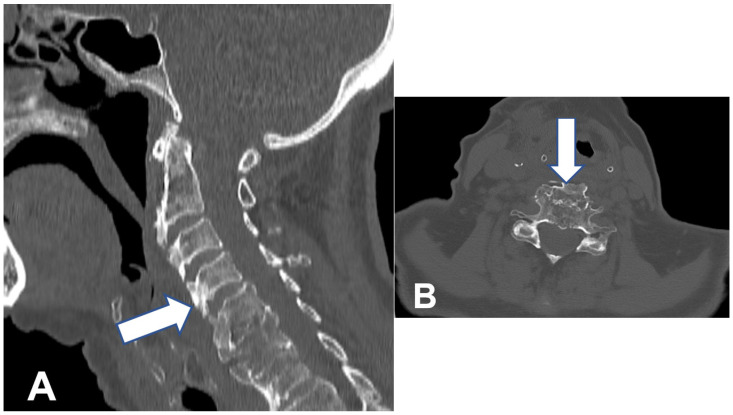

背景/目的:弥漫性特发性骨骼肥厚症(DISH)也被称为foretier - rotes - querol综合征。DISH的病因尚不清楚。DISH的特点是脊柱前纵韧带骨化。该疾病最常累及的区域是脊柱的胸椎区域。DISH在大多数情况下是无症状的。如果颈椎受累,最常见的症状是吞咽困难和呼吸困难。颈椎区的骨化最常发生在脊柱的下节段。病例报告:作者报告了一位92岁的女性病毒症患者(身体质量指数(BMI)为17;在过去的6个月里她的体重减少了13%)。患者行前骨赘C2-T1切除术。结果:在一年的随访中,患者体重增加(BMI-20),并恢复了固体食物的摄入能力。据我们所知,这是接受DISH手术治疗的年龄最大的患者。结论:老年患者如出现吞咽困难或呼吸困难,应进行颈椎检查。如果诊断为DISH是安全的,则应考虑有效的手术治疗。

Background/Objectives: Diffuse idiopathic skeleton hyperostosis (DISH) is also known as Forestier-Rotes-Querol syndrome. The etiology of DISH is unknown. DISH is characterized by ossification of the anterior longitudinal ligaments of the spine. The area most frequently involved in the disease is the thoracic region of the spine. DISH in most cases is asymptomatic. If the cervical spine is involved, the most common symptoms are dysphagia and dyspnea. The ossifications in the cervical region of the spine are localized most frequently in its lower segments. Case presentation: The authors present the case of a 92-year-old cachectic female patient (body mass index (BMI) of 17; lost 13% of her body weight within the last 6 months). The patient underwent resection of the anterior osteophytes C2-T1. Results: At one-year follow up, the patient had gained weight (BMI-20) and regained her ability to consume solid products. To our knowledge, this is the oldest patient treated surgically for DISH. Conclusions: If dysphagia or dyspnea appears among elderly patients, cervical spine inspection should be conducted. If DISH is diagnosed safe, effective surgical treatment should be considered.